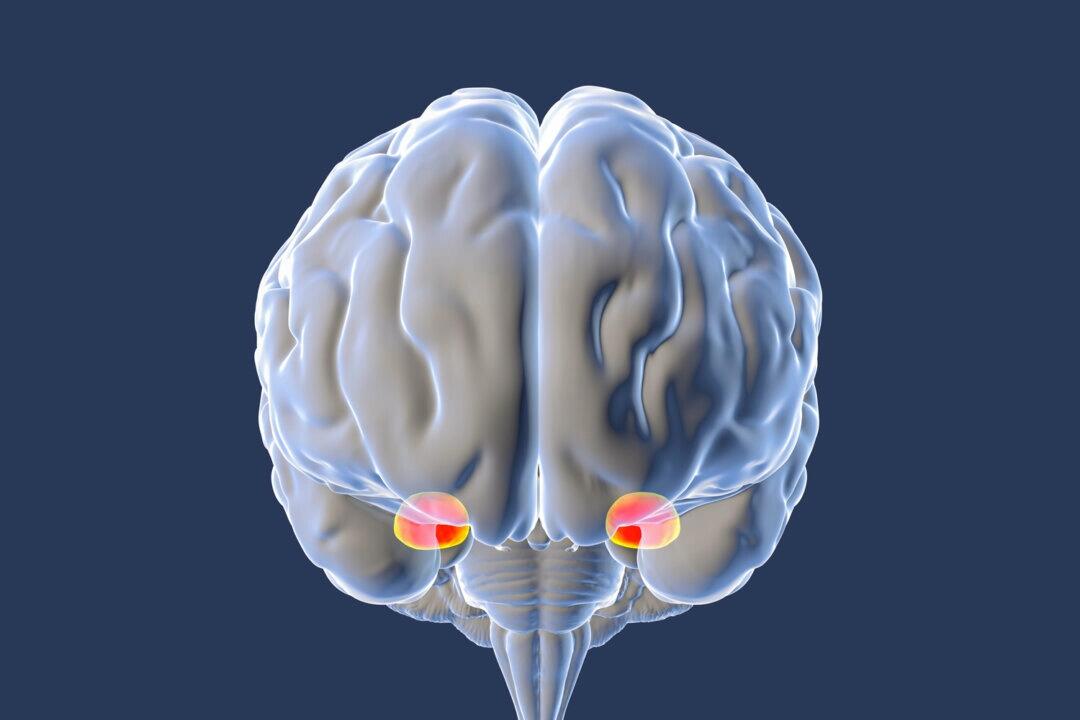

This surge of anxiety stems from your brain’s fight-or-flight response. It is designed to protect us from threats, but modern life sets it off every time we get stuck in traffic or think our coworker is upset with us. When activated repeatedly, it can fuel high blood pressure, weakened immunity, anxiety disorders, and burnout.

The amygdala becomes harder to regulate when a person is exposed to repeated uncertainty or alarm.

At the center of our fear response is the amygdala, an almond-sized structure deep in the brain responsible for detecting threats and triggering rapid emotional reactions. However, it can be trained to calm down.

How can something the size of an almond cause so much trouble? Because its job lies at the heart of human experience. The amygdala is the region of the brain associated with emotional processing, and it constantly scans for threats like a smoke detector ready to sound the alarm.

When this protective system becomes hypersensitive, it can trick the brain into perceiving threats where none exist. The amygdala doesn’t distinguish between real-time danger and imagined scenarios. It can be activated by memories, sensory cues, or hypothetical fears, such as standing near the edge of a high balcony, even if you’ve never fallen.